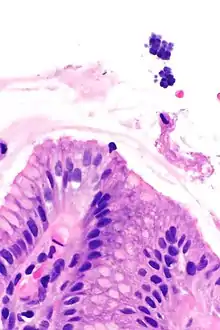

Gastric mucosa and Sarcina on upper right. H&E stain. | |

Sarcina is a genus of Gram-positive cocci bacteria in the family Clostridiaceae.[2][3][4] A synthesizer of microbial cellulose,[5] various members of the genus are human flora and may be found in the skin [6] and large intestine.[7] The genus takes its name from the Latin word "sarcina," meaning pack or bundle, after the cuboidal (2x2x2) cellular associations they form during division along three planes.[8]